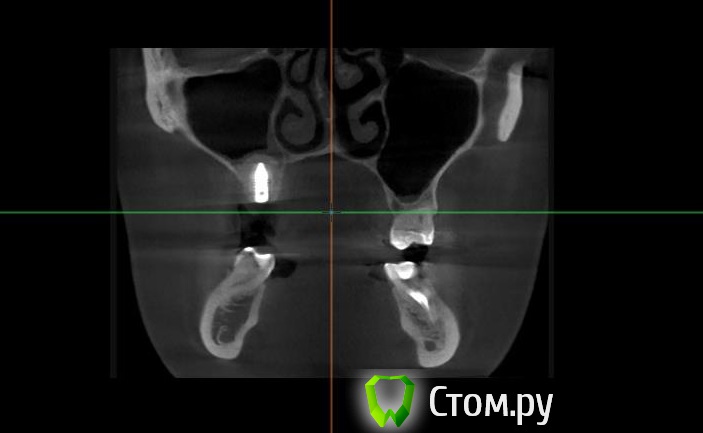

Майло Опубликовано 18 марта, 2014 Автор Поделиться Опубликовано 18 марта, 2014 (изменено) Здравствуйте, наконец сделала кт. Сегодня появилась небольшая боль над правой бровью (после лазера прошла, к вечеру появилась опять). Насморк и заложенность присутствуют. Еще сегодня опять поговорила со своим хирургом имплантологом. По симптомам сказал, что похоже присоединилась какая-то лор болячка и наверное надо сходить к лору. По кт сказал, что все нормально. Немного сужена пазуха справа, но учитывая, что я аллергичная, это нормально. Про капли типа Полидекса, сказал спросить у лора. Завтра я делаю последний лазер, по прежнему промываю нос Отривином Бэби (мне так удобней), пью кларитин, "выбиваю" нос по необходимости, но стараюсь пореже (2-3 раза в день). Еще он отдал кт через 2 недели после имплантации, на всякий случай прикреплю и этот снимок. Самый первый снимок кт был сделан через 2 недели после имплантации. Второй и третий сегодня. Подскажите, я так понимаю данное кт не показывает есть ли у меня гайморит? (к лору смогла записаться аж на 26-е) И все равно хотелось бы узнать ваше мнение по поводу состояния имплантов, есть ли там воспаление или "нагноение"? Изменено 18 марта, 2014 пользователем Майло Ссылка на комментарий

Майло Опубликовано 18 марта, 2014 Автор Поделиться Опубликовано 18 марта, 2014 (изменено) Решила еще добавить пару кадров своих пазух, вначале показалось что справа что-то есть (рис1), потом поняла это костный материал и импланты (рис2). Надеюсь так должно быть. И еще вопрос, может и "тупой", такое яркое свечение имплантов, особенно заметно на фото в профиль, это нормально? Изменено 18 марта, 2014 пользователем Майло Ссылка на комментарий

Bier Опубликовано 18 марта, 2014 Поделиться Опубликовано 18 марта, 2014 выглядит все неплохо, и пазуха чистая. Гайморита у вас нет. Сходите к ЛОРУ 2 Ссылка на комментарий

Майло Опубликовано 19 марта, 2014 Автор Поделиться Опубликовано 19 марта, 2014 (изменено) выглядит все неплохо, и пазуха чистая. Гайморита у вас нет. Сходите к ЛОРУСпасибо. А такие затемнения вокруг имплатов, это нормально? Изменено 19 марта, 2014 пользователем Майло Ссылка на комментарий

red_butler Опубликовано 19 марта, 2014 Поделиться Опубликовано 19 марта, 2014 Да, это артефакты вызванные металлом Ссылка на комментарий